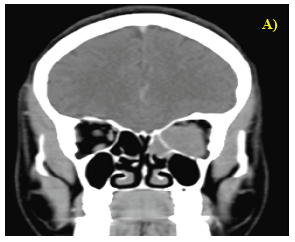

Contrast-enhanced computed tomography (CECT) of the paranasal sinuses (PNS) and orbits revealed a large, well-defined, homogeneously enhancing soft-tissue density lesion involving both the intra and extraconal spaces of the left orbit, extending up to the orbital apex. The left optic nerve was displaced supero laterally by the lesion. Additionally, hypoenhancing lesions were noted in the bilateral sphenoid sinuses and the left posterior ethmoid sinus (Figures 1 & 2).